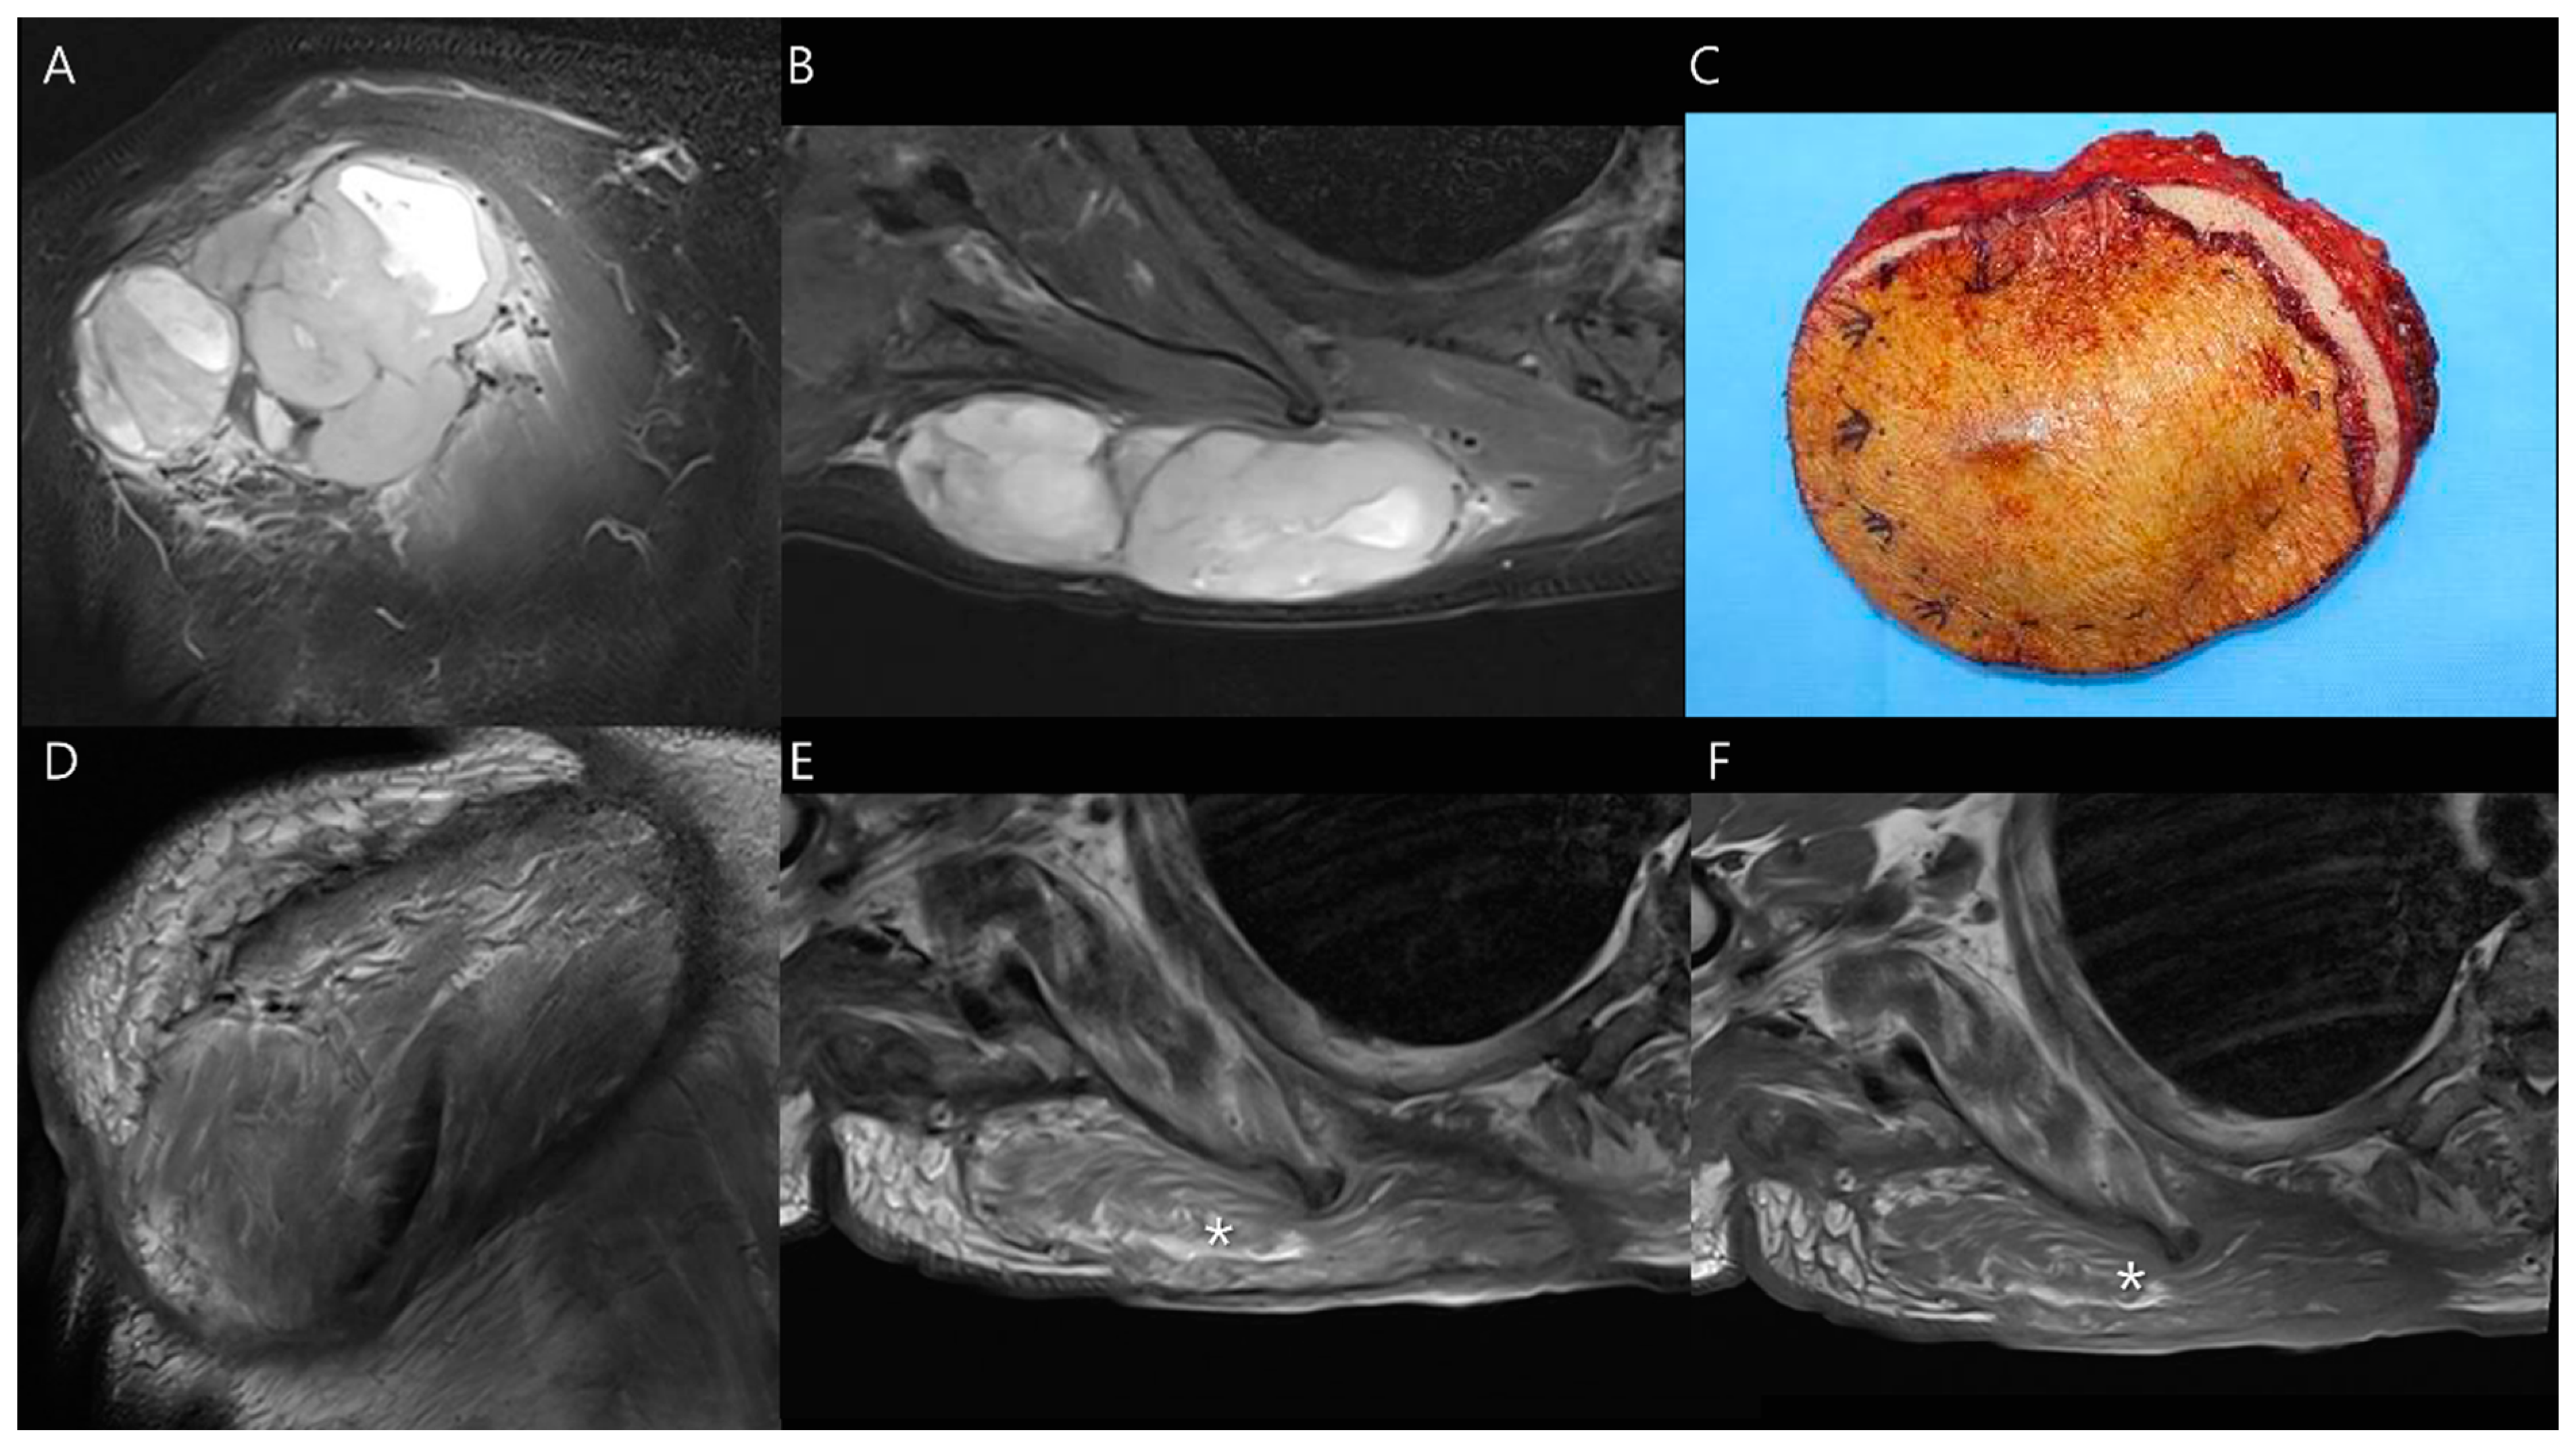

3.2. Soft Tissue Tumors

4.2. Postoperative Complication of Reconstructive Surgery for Soft Tissue Tumors

4.2.1. Seroma

4.2.2. Hematoma

- Olapoju, O.M.; Botros, J.; Damani, B.; Tiesenga, F. Chronic Expanding Hematoma in the Upper Extremity: A Case Report on Diagnostic and Management Challenges. Cureus 2024, 16, e62330. [Google Scholar] [CrossRef]

- Liu, P.T.; Leslie, K.O.; Beauchamp, C.P.; Cherian, S.F. Chronic expanding hematoma of the thigh simulating neoplasm on gadolinium-enhanced MRI. Skelet. Radiol. 2006, 35, 254–257. [Google Scholar] [CrossRef]

- Reid, J.D.; Kommareddi, S.; Lankerani, M.; Park, M.C. Chronic expanding hematomas. A clinicopathologic entity. JAMA 1980, 244, 2441–2442. [Google Scholar] [CrossRef]

- Serra Del Carpio, G.; Tapia Viñé, M.; Torena, N.; Bernabeu Taboada, D. Chronic expanding hematoma. Radiología 2023, 65 (Suppl. 2), S78–S82. [Google Scholar] [CrossRef]

- Galantini, G.; Mushtaq, B.; Ottaway, J.; Long, C.D. Successful Treatment of a Chronic Recurrent Expanding Hematoma of the Thigh. Plast. Reconstr. Surg. Glob. Open 2024, 12, e6133. [Google Scholar] [CrossRef] [PubMed]